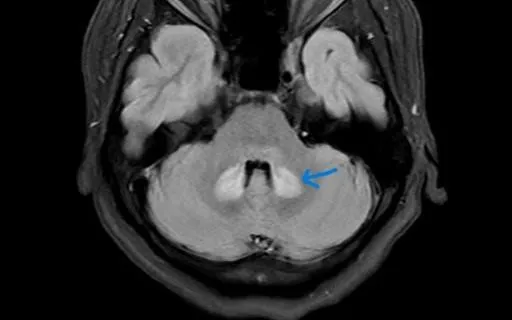

Kết quả siêu âm tại Bệnh viện Bạch Mai cho thấy viêm tinh hoàn và mào tinh hoàn, nguy cơ teo tinh hoàn nếu không xử trí kịp thời. BSCKII. Nguyễn Thị Ngọc Chi cho biết: "Quai bị ở nam giới dậy thì và trưởng thành dễ gây viêm tinh hoàn, có thể dẫn đến vô sinh".